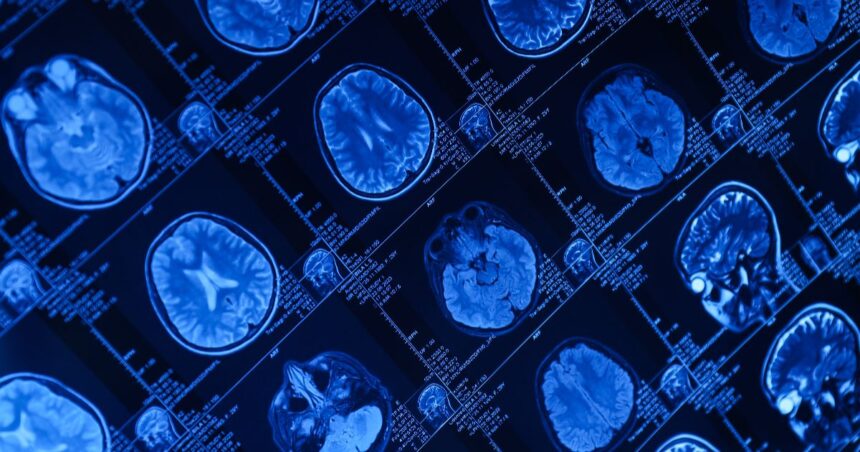

Functional MRI is a brain imaging test that shows how your brain works in real time.

Functional MRI, also called fMRI, measures brain activity by tracking changes in blood flow.

Unlike a regular MRI, which shows brain structure, this test shows brain function.